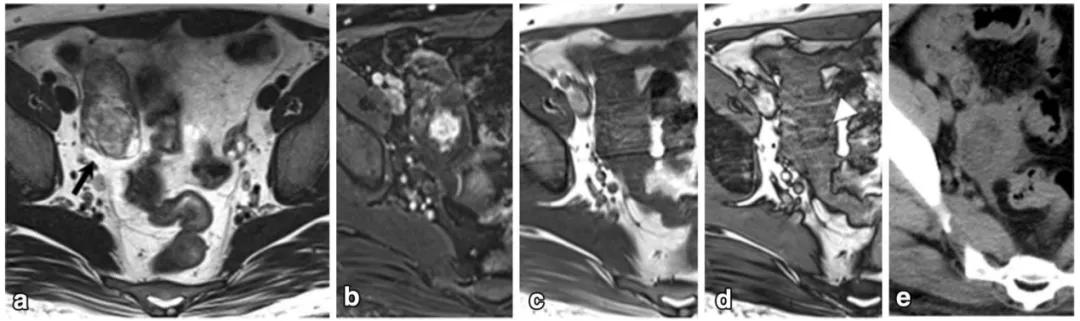

女性,36 岁,睾酮升高,类固醇细胞瘤。T2WI 示右卵巢可见不均匀稍高信号肿物(图 a),增强扫描早期明显强化(图 b)。T1WI 同相位(图 c)及反相位(图 d)可显示肿物内脂质成分,相应 CT 图像呈低密度(图 e)